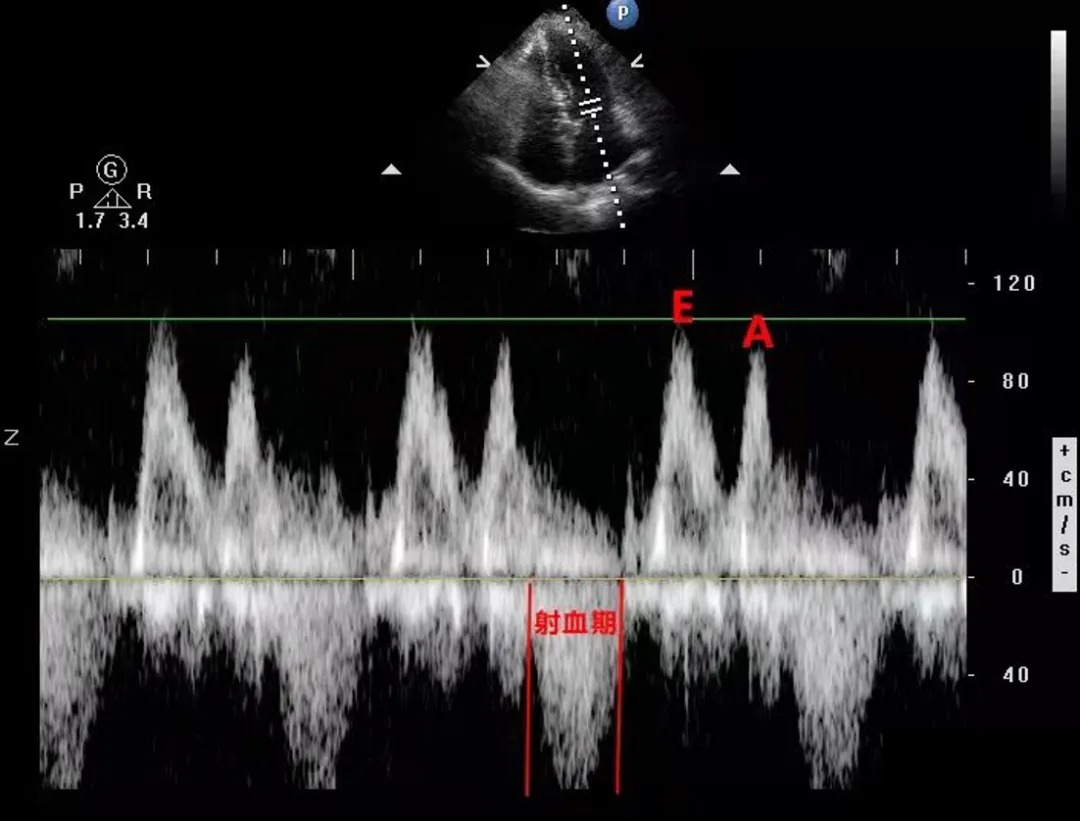

快速充盈期的时长要大于心房收缩期的时长,因此可以通过波形时长来区分E、A峰,占时长的是E峰,短的是A峰,如图所示:

但是当心率比较快或者心率不齐的时候,两个波峰时长相近或呈现单峰,此方法就不太适用了,如图:

那么此时我们可通过心动周期来进行分析

如上图所示射血期的后面紧跟的一定是快速充盈期,而不是心房收缩期。

所以只要确定了射血期,那么紧跟在射血期后面的就是快速充盈期,对应的波峰也即E峰,然后接着才是心房收缩期,也即A峰。